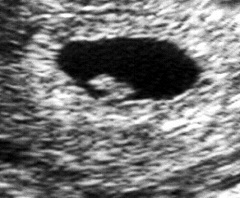

УЗИ на 6 неделе беременности позволяет узнать количество плодов в полости матки (от двух в случае многоплодной беременности), а также оценить скорость роста будущего малыша. Внешне плод похож на боб фасоли, и можно отчетливо услышать его сердцебиение.

На УЗИ на 6 неделе беременности видно, как отчетливей вырисовываются черты будущего лица – челюсть, нос, рот, ушные раковины. Уже на таком раннем сроке закладываются зачатки молочных зубов. Глаза, которые до этого находились с обеих сторон головы в виде зачатков, сближаются друг с другом и во фронтальную плоскость. Их размер остается довольно большим по сравнению с другими органами.